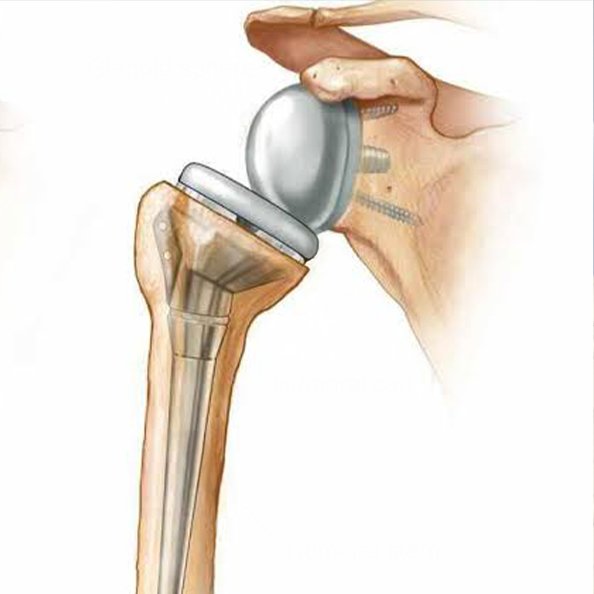

Shoulder Replacement Surgery

Reliable shoulder replacement surgery for damaged joints, reducing pain, enhancing strength, and improving long-term shoulder function and overall mobility.